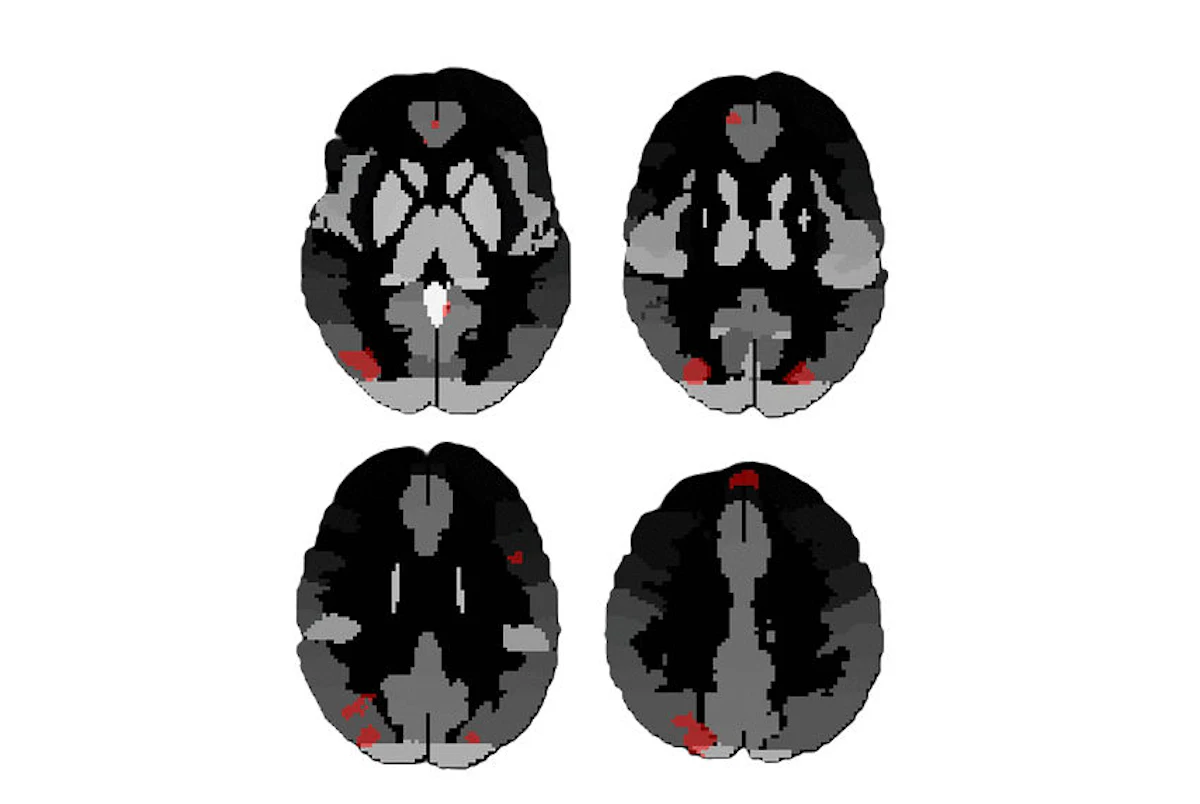

Resting-state fMRI analysis reveals impact of blast exposures

Functional MRI (fMRI) is further revealing changes in the brain caused by repetitive blast exposure and highlights the need to rethink "mild" brain injuries across society, according to research published April 1 in Radiology.

A team led by neuroradi… [3352 chars]